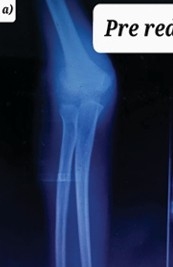

Prone Reduction Technique of Pediatric Gartland Type 2 Extension Supracondylar Fractures of Humerus in an Outpatient Low-Resource Setting

Vishwas Kadambila , S Karthik , Erukula Saikrishna , A Chandrahas , B S Sudharshan Abhishek , John Joe Jacob

………………………………p.392-398